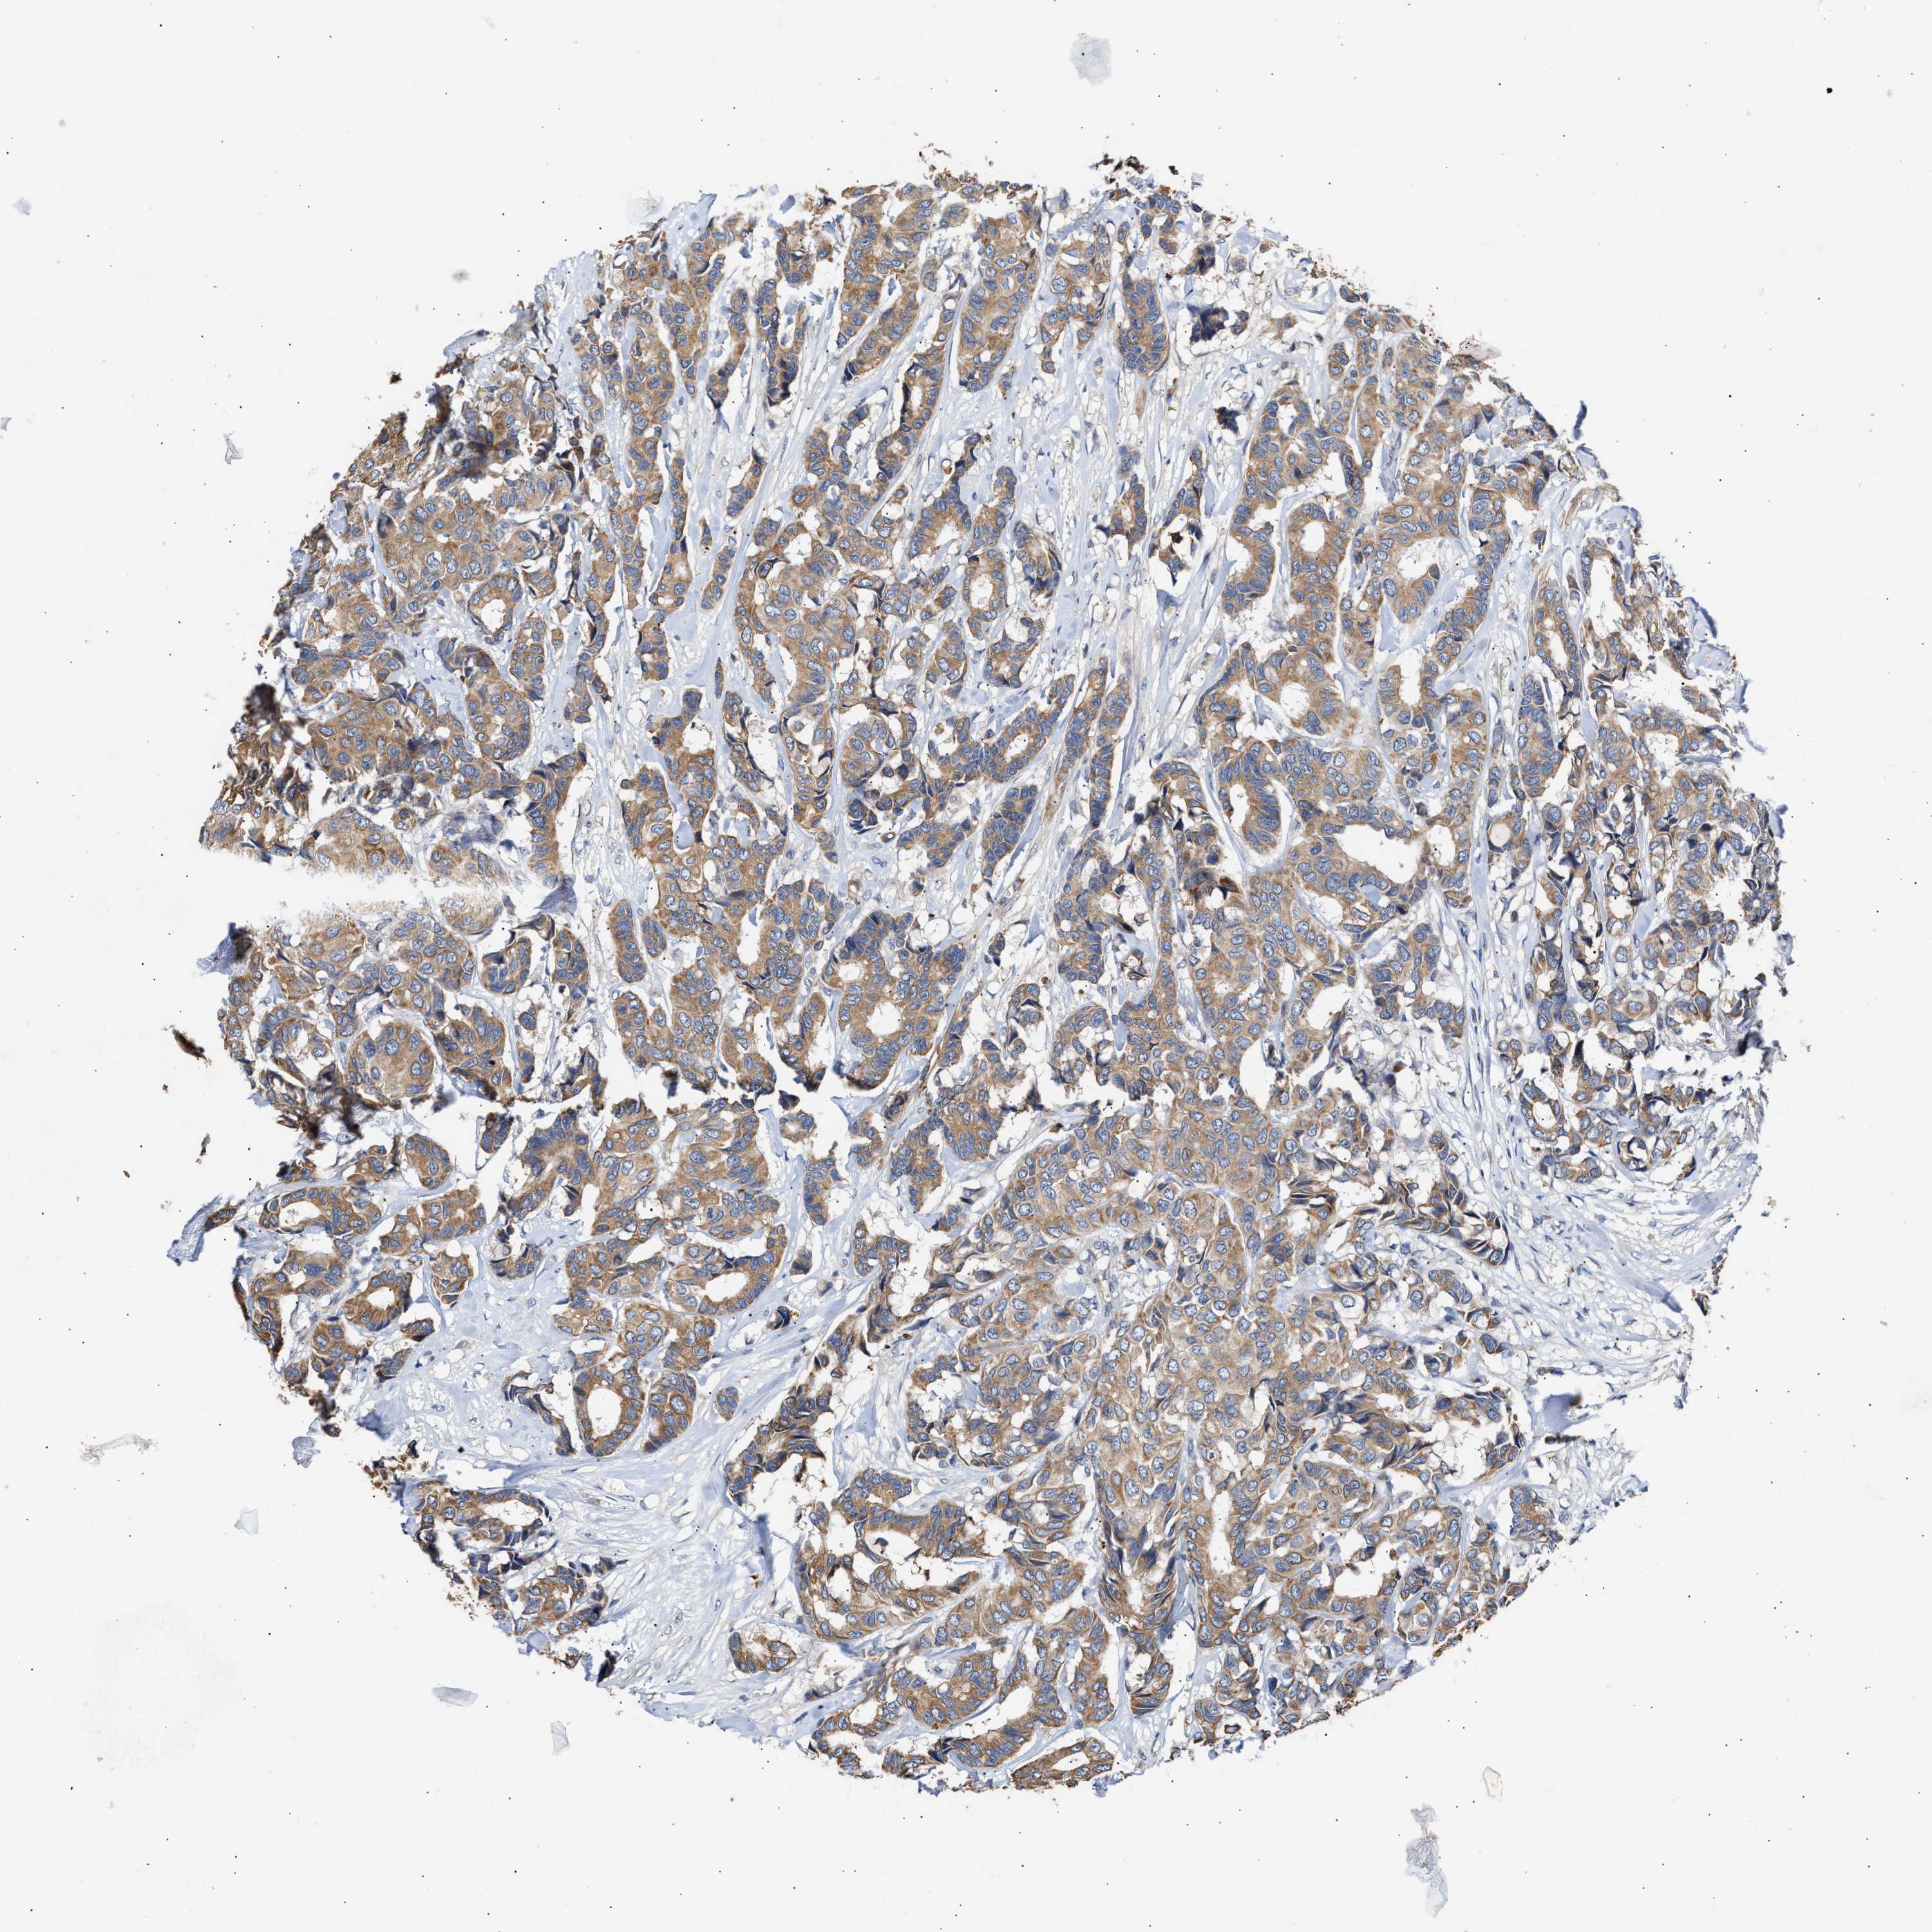

CANCER BREAST CANCER Show tissue menu

BRCA TCGA BRCA VALIDATION PROTEIN EXPRESSION

ANTIBODIES

AND

VALIDATION